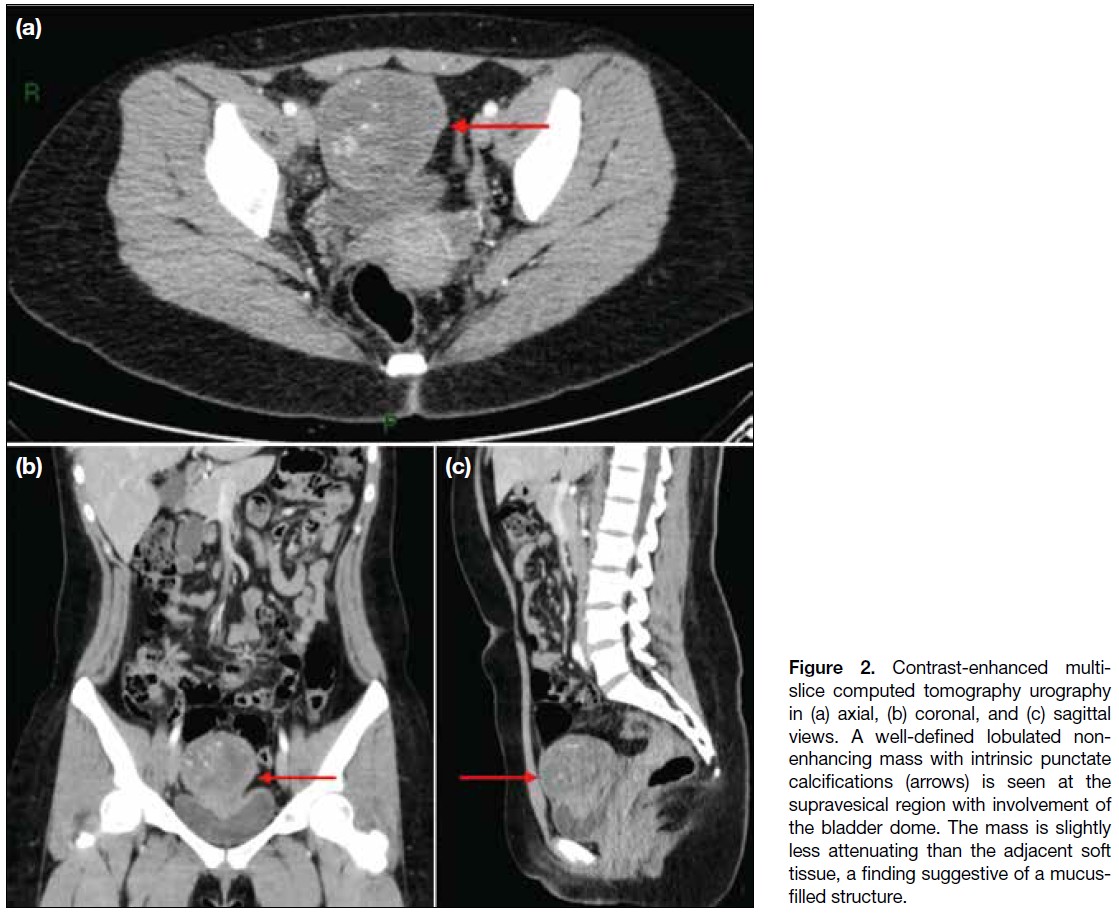

A subsequent computed tomography (CT) urography

(Figure 2) revealed a lobulated, heterogeneously

enhancing mass in the supravesical region with associated

calcifications. The mass abutted the bladder dome with

obliteration of the fat plane, suggesting infiltration. A

1.8-cm enlarged lymph node was also noted in the right

paravesical region. A urachal neoplasm was considered.

Figure 2. Contrast-enhanced multi-slice

computed tomography urography

in (a) axial, (b) coronal, and (c) sagittal

views. A well-defined lobulated non-enhancing

mass with intrinsic punctate

calcifications (arrows) is seen at the

supravesical region with involvement of

the bladder dome. The mass is slightly

less attenuating than the adjacent soft

tissue, a finding suggestive of a mucus-filled

structure.

CT imaging can be used to confirm the ultrasonographic

findings or serve as the first-line imaging to evaluate

local disease, tumour extension, and the presence of

pelvic lymph node involvement or distant metastases.[7]

A key diagnostic feature of urachal adenocarcinoma on CT is its supravesical midline location. The mass

often demonstrates predominantly low attenuation,

attributable to its mucinous content found on pathological

examination. Calcifications are also commonly seen in

mucinous tumours.[9] These findings closely correspond

to the appearance and location of the tumour in the index

patient’s CT urography.